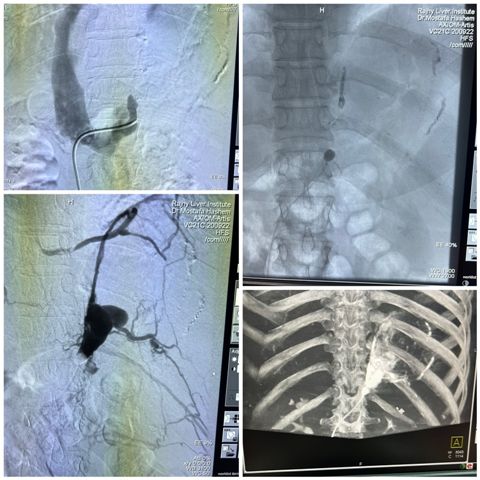

وفى السياق ذاته أعلن الدكتور علاء عطية عميد كلية الطب و رئيس مجلس إدارة مستشفيات أسيوط الجامعية عن تحقيق مستشفيات جامعة أسيوط  انجاز و سبق علمي جديد من خلال نجاح فريق طبي بوحدة الأشعة التداخلية بقسم الأشعة بمستشفيات جامعة أسيوط بعمل تقنية غلق دوالي المعدة عن طريق الأشعة التداخلية باستخدام البالونات ولأول مرة على مستوى مستشفيات الجمهورية و الذى يضاف إلى سجل انجازاتها الطبية و العلاجية و تأكيداً على التعاون و التكامل بين المستشفيات فى مختلف التخصصات لتقديم و تطوير الرعاية الطبية المقدمة للمرضى المترددين عليها من مختلف محافظات الصعيد.

أوضح الدكتور شريف كامل مدير مستشفى الراجحى للكبد والجهاز الهضمى أنه تمت إجراء العملية بوحدة الأشعة التداخلية بمستشفى الراجحى الجامعى للكبد بقيادة الدكتور مصطفى هاشم رئيس قسم الأشعة التشخيصية و التداخلية وضم الفريق الطبي  كلاً من  الدكتور رامي محمد  مدرس الأشعة التشخيصية و التداخلية، و الدكتور سيد حسن مدرس الأشعة التشخيصية و التداخلية ، و الدكتور ممتاز ثابت  مدرس الأشعة التشخيصية و التداخلية ، و الدكتور مصطفى أحمد مدرس مساعد  الأشعة التشخيصية و التداخلية.

وأوضح الدكتور مصطفى هاشم أن هذه التقنية الحديثة تستخدم فى علاج حالات معينة من دوالي المعدة و التي لا يمكن التعامل معها من خلال مناظير المعدة و تتم ولأول مرة بمستشفيات جمهورية مصر العربية، موجهاً كل الشكر لطاقم التمريض و طاقم الفنيين و المساعدين بوحدة الأشعة  بمستشفى الراجحى.